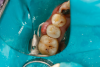

Respecting the inverse square law, the resident doubled the light-curing time to ensure good adhesive polymerization in the deep box. To facilitate the matrix band providing deep access  (Paraband, Practicon; alternatively: Greater Curve matrix band; Greater Curve), the clinicians needed to remove the dam. Assurance of a dry field was accomplished by placement of bilateral dry angles that stem saliva flow from Stensen's ducts. A swedopter device was placed under the tongue to suction saliva from the sublingual and submandibular glands. Figure 17 shows the gingival area closure accomplished with the Paraband "Elizabethan collar effect"; no wedging is possible, so this Tofflemire type band provides a tight gingival seal by virtue of the band's unusual geometry. In Figure 18, the comfort of injection of the dual- cured bulk-fill flowable utilizing the bendable 20-gauge needle can be noted; it would not be possible to fill this with a paste-type universal composite. Subsequent to a 90-second self-cure phase during which the surface cannot be disturbed, the resident placed starting pits in the mesial central and distal pit areas with the medium acorn of the Occlusinator PRO bur system (StraussUSA; alternatively: R.A.P.T.O.R. Acorn, Henry Schein) (Fig- ure 19). Figure 20 shows the pits created at uniform depth facilitated by the limit stops on the burs. The acorn now is moved in a pit-to-pit pattern that created the planes that form the triangular and oblique ridges as well as the marginal ridges (Figure 21). After the planes were formed, a X-mas tree-shaped diamond bur was used to refine and prepolish the planes formed by the acorn (Figure 22). Refinements such as secondary anatomy can be placed using the mini-acorn (Figure 23). Figure 24 shows a Brownie polisher reshaped to a straight-sided X-mas tree bur that is used to polish the planes, pits, and ridges. In Figure 25, a Greenie polisher is shown that also has been reshaped to be a straight-sided X-mas tree polisher. Both are used at 50,000 to 100,000 rpm and with a copious water spray. Final polish is accomplished with a latch bristle brush coated with TopDotz polishers (Dental Ventures of America; alternatively: Shammy Bright Composite Polishing Paste, Kerr Dental) (Figure 26). As shown in Figure 27, the pure diamond comes in pellet form to facilitate good asepsis. The last polish is applied with a dry latch-type cotton buff (Figure 28). In Figure 29, note the anatomy formed by this technique. It is apparent that this resident accomplished a more than satisfactory result, as evidenced by the post-treatment radiograph (Figure 11).

Fig 17. “Elizabethan collar effect” of matrix band.

Figure 17

Fig 18. Matrix band in place, injection filled with dual-cure bulk-fill flowable composite.

Figure 18